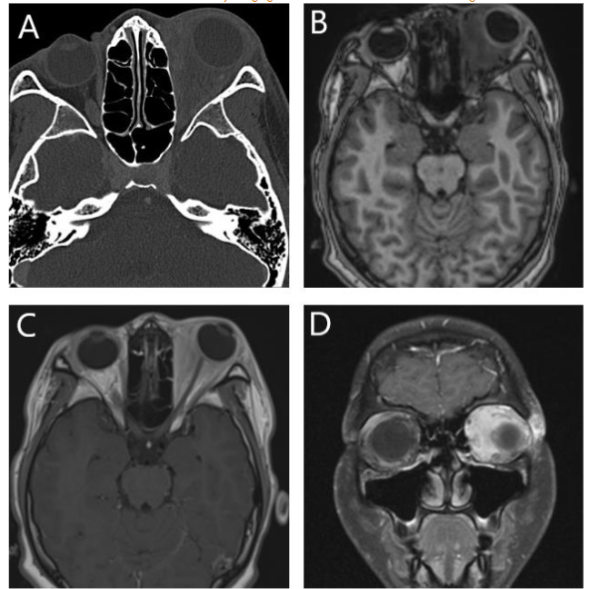

An orbital CT scan showed severe right orbital proptosis, right-sided pre- and post-septal soft tissue thickening with intraconal/retrobulbar space extension and diffuse thickening of the adjacent bone secondary to chronic inflammation without erosion. There was also diffuse paranasal sinus mucosal thickening.

Orbital MRI provided a clearer characterization of diffuse retro-orbital soft tissue thickening, involving the fat, extraocular muscles, and lacrimal glands, leading to pronounced right orbital proptosis and globe eversion. The right globe was flattened with optic nerve stretching. The retrobulbar mass extended posteriorly into the orbital apex without cavernous sinus involvement, and there was also further extension into the lateral face, affecting the temporalis muscle.

Langerhans cell histiocytosis (LCH), Erdheim-Chester disease (ECD), and Rosai-Dorfman disease (RDD) are different subtypes of histiocytosis that can potentially involve the orbit. Langerhans cell histiocytosis (LCH) is the most prevalent form of histiocytosis, impacting multiple organs and systems, with the lungs and bones being the most commonly affected, particularly in pediatric patients. Orbital involvement occurs in approximately 20% of LCH patients, often presenting as lesions in the bony orbit, most frequently in the upper outer region. These lesions can extend to nearby soft tissue, leading to symptoms such as proptosis, swelling, and restricted eye movement. Orbital LCH is more common in children than in adults, but it can also occur in adults. The presence of additional destructive skull base lesions can be a valuable clue in narrowing down the differential diagnosis. In this case, the absence of adjacent osseous erosions and other systemic indicators of LCH helped to lower LCH on the differential diagnosis list.

Erdheim-Chester disease (ECD) is a rare subtype of histiocytosis that predominantly affects the skeletal system in more than 95% of cases. Orbital involvement occurs in 25% of ECD patients, typically appearing on imaging as an infiltrative intraconal or retrobulbar mass, leading to exophthalmos.

Rosai-Dorfman disease (RDD), also known as sinus histiocytosis with massive lymphadenopathy, is a benign, self-limited condition that primarily affects lymph nodes. As its name suggests, the paranasal sinuses are the most common sites of extranodal involvement. Orbital involvement is seen in approximately 7% of patients, typically manifesting as unilateral, infiltrative, and enhancing retro-orbital soft tissue masses affecting the extraocular muscles, retro-orbital fat, and lacrimal gland. This results in proptosis, with contrast enhancement that may be either uniform or heterogeneous.